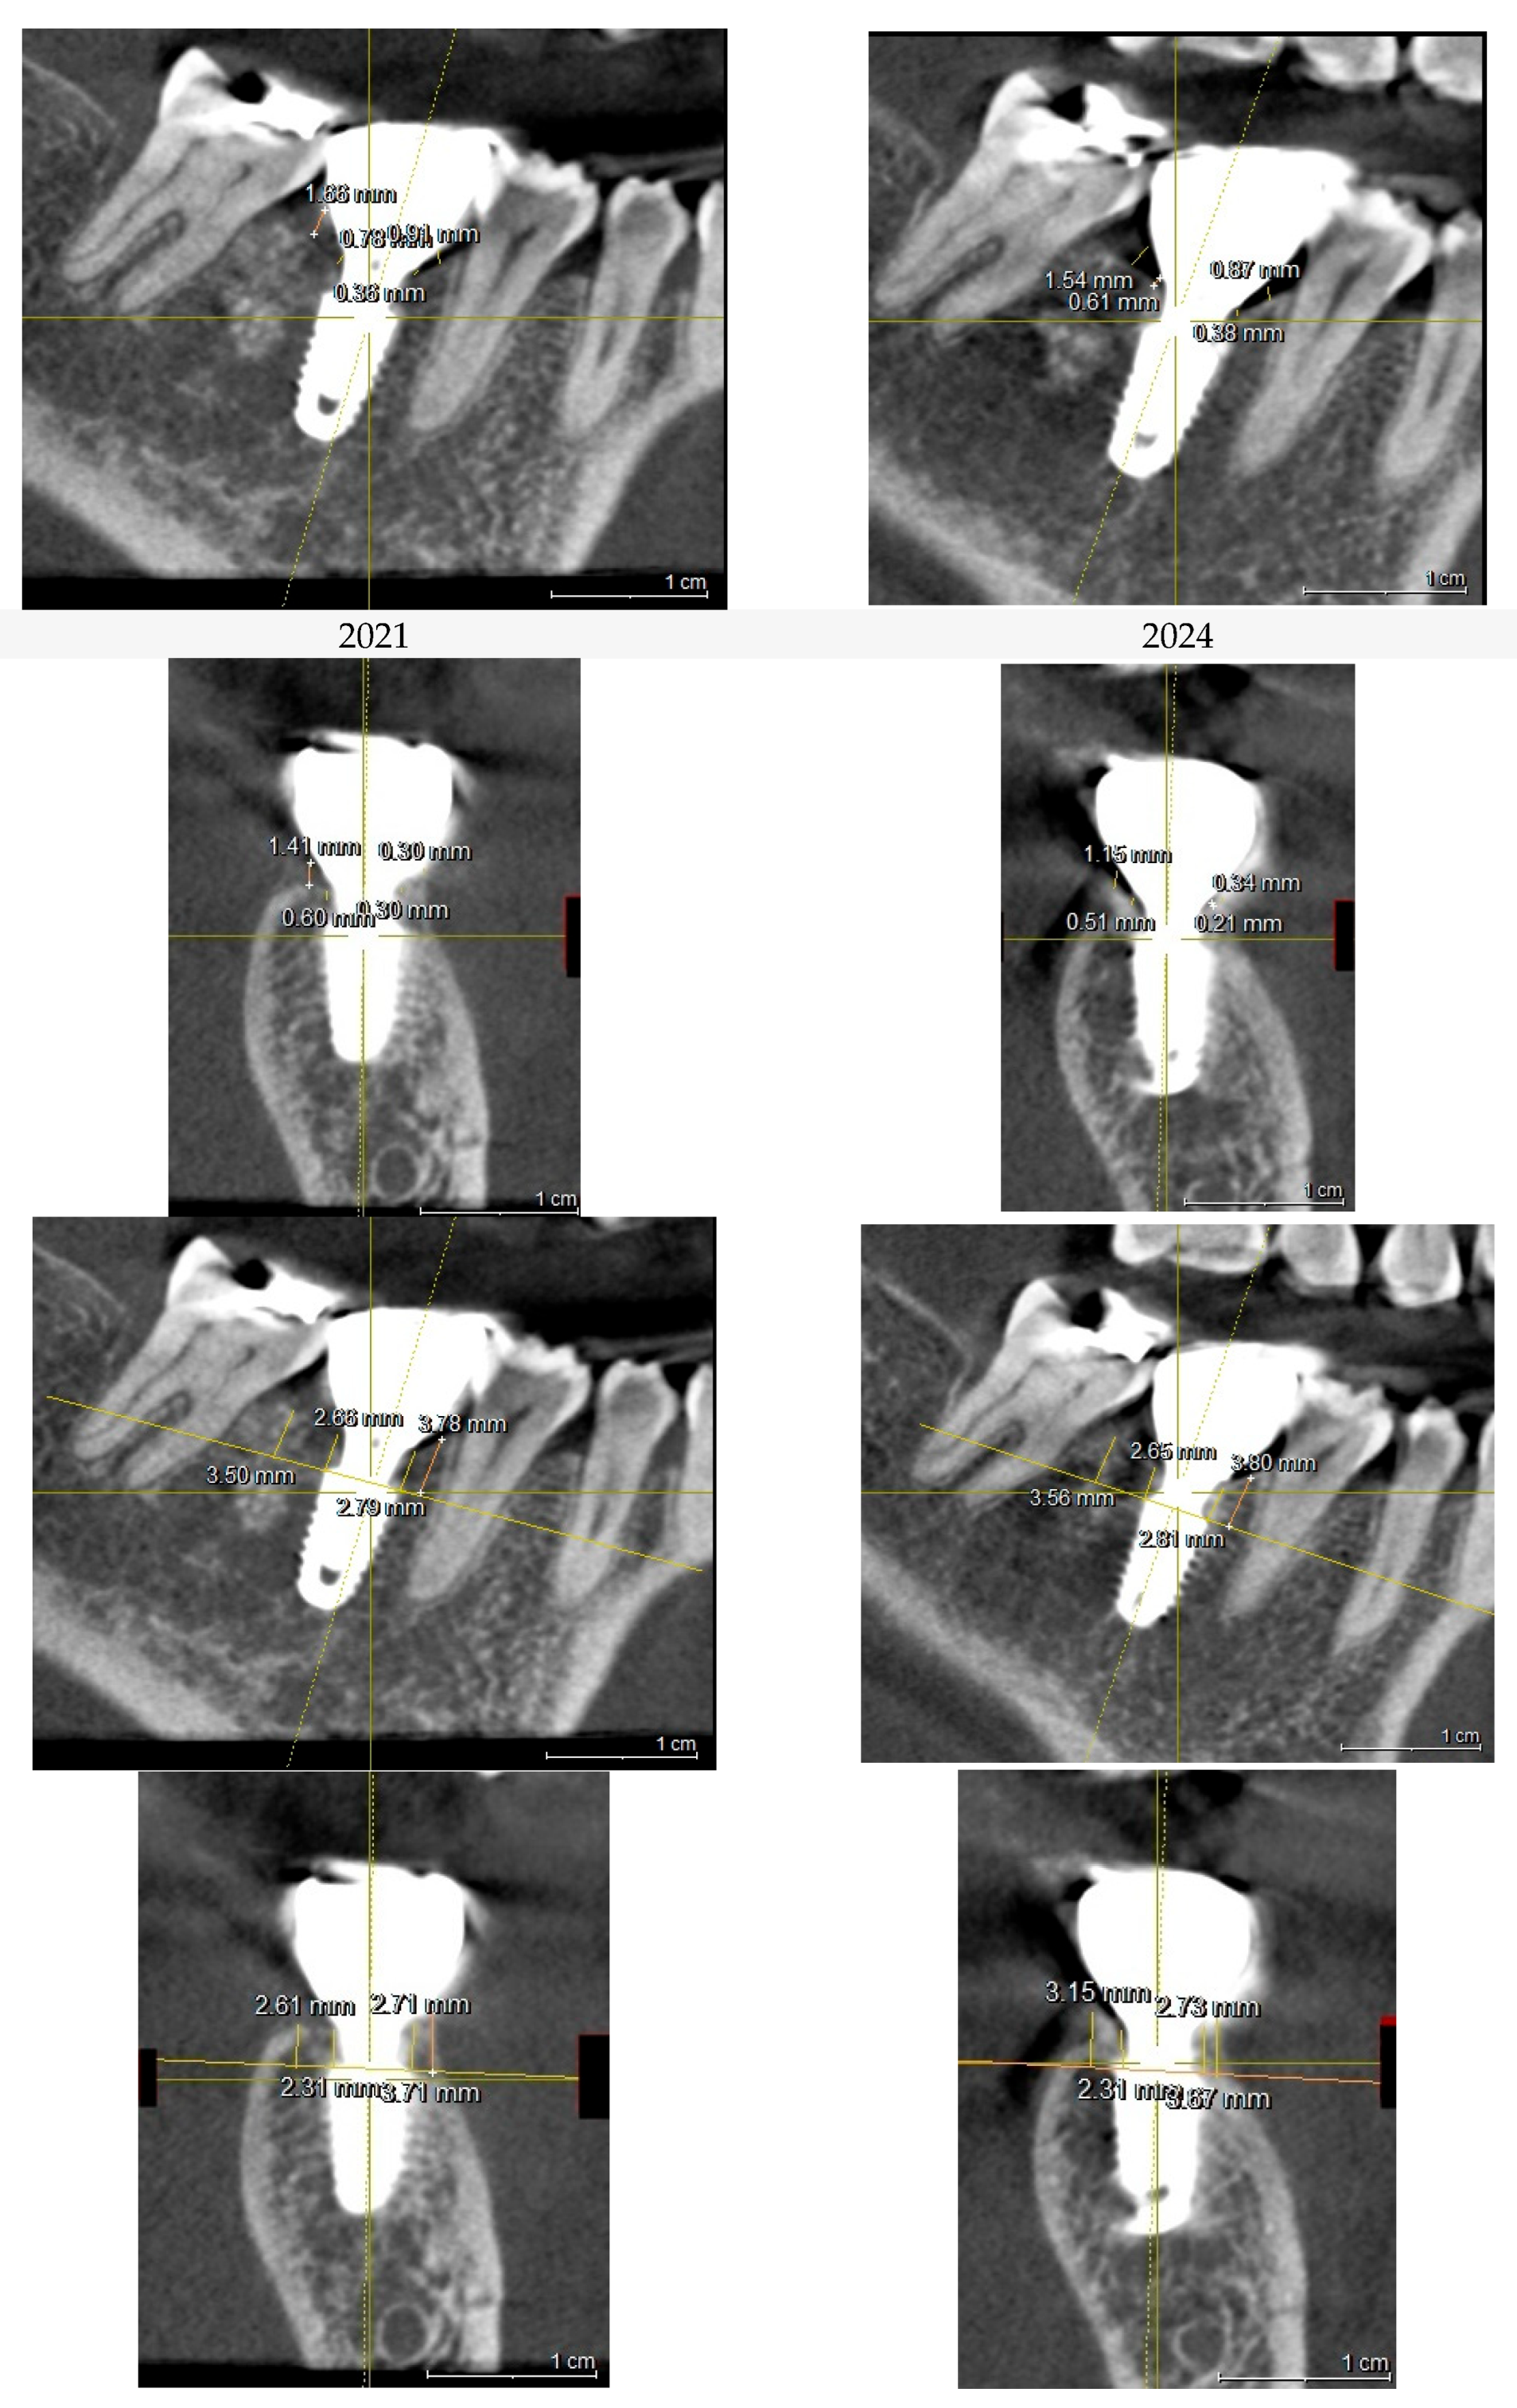

The post-revision evaluation provides significant insights into the structural changes in peri-implant soft tissue and their impact on implant health. Figure 10 compares X-rays from October 2021 and July 2024, illustrating a marked decrease in the Crest to Restoration Distance (CRD) following the restoration modification. (Figure 10) After the reduction achieved by modifying the implant restoration, the gap can now be regarded as entirely filled by peri-implant soft tissue, without voids. From this observation, it can be suggested that maintaining the CRD within a critical range is essential for achieving a stable biological seal, as it ensures the peri-implant soft tissue provides an effective barrier against external irritants and bacterial infiltration.

Figure 10. Comparison of X-rays taken in October 2021 and July 2024 after the restoration revision, demonstrating a decrease in the CRD. When the CRD is maintained within the critical range, it can be inferred that the gap space is occupied exclusively by peri-implant soft tissue, without voids, and the GRD can be represented as Soft Tissue Thickness (STT).